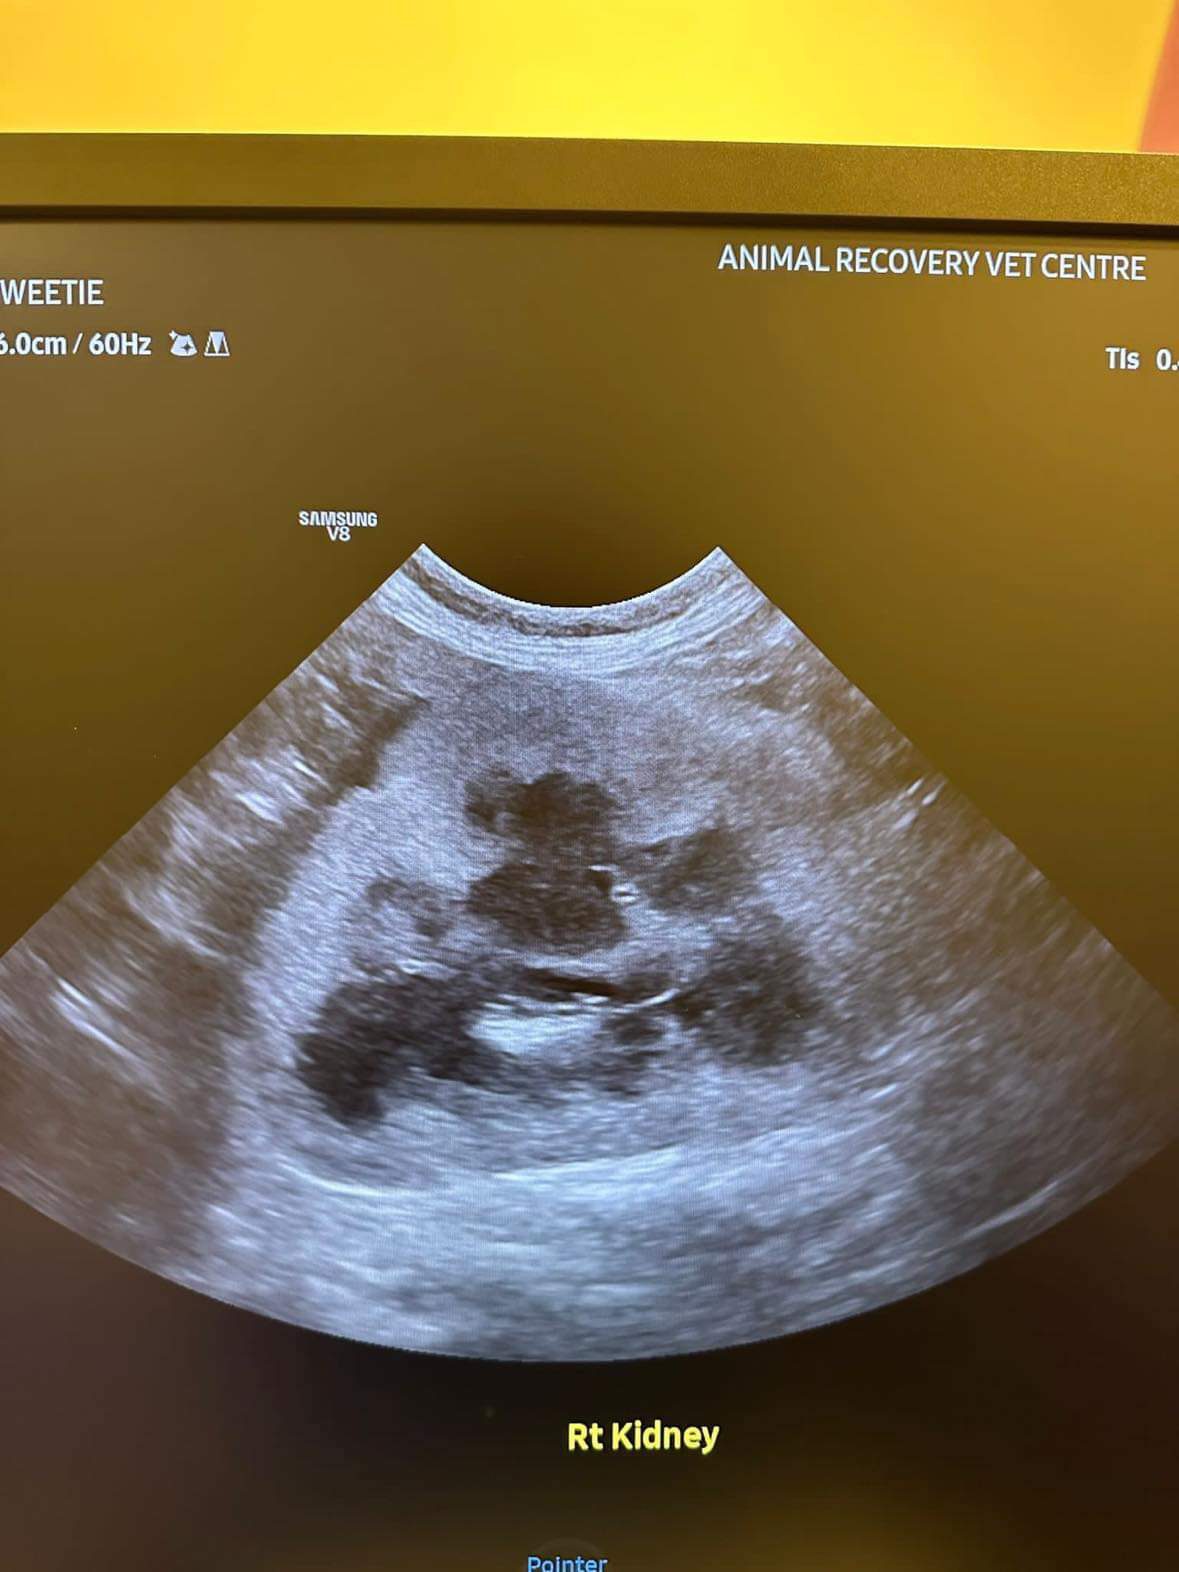

U/s done and basically not much use to me, liver got issue, kidneys got some fatty deposits which is diabetic, so insulin correct. Gall bladder got some obstruction so just start urofalk. All in must put o tube. Dr Daniel do it.

her left kidney 8.0cm, right 7.0cm also double the normal size

Dr ym scan sweeties, dr flo not involve, both got free fluid ard the kidneys, left kidney is extremely abnormal, right kidney abnormal.